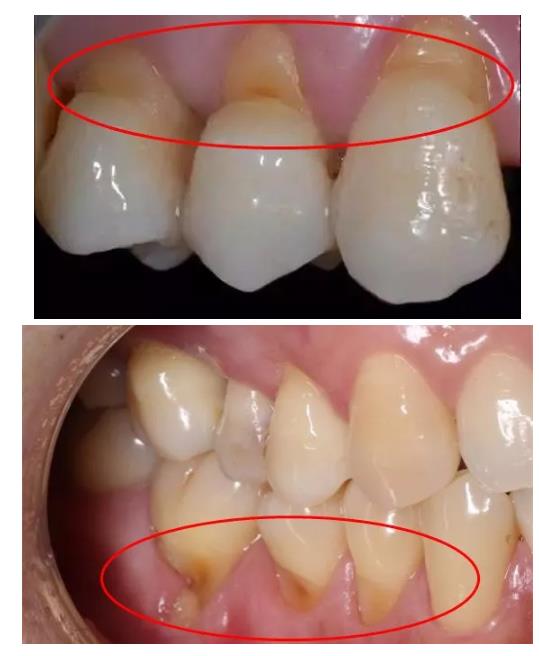

早晚刷牙的道理大家都懂,可是掌握正確方法的人卻不多,有多少小伙伴是像上圖這樣,拿著牙刷用力在嘴巴里橫著來回撥拉幾下了事,力道之迅猛猶如狂風(fēng)過境。快停下,這樣刷牙牙齒遲早會被你刷斷的!

楔狀缺損該如何治療?

對于組織缺損較少的患者,局部不需要特殊處理。但要避免橫刷,并選用較軟的牙刷和磨料較細的牙膏。可選用與牙齒顏色近似又有一定粘接性的復(fù)合樹脂或玻璃離子粘固粉等將楔狀缺損補好,以防繼續(xù)發(fā)展。對于重度缺損而引起牙髓炎、根尖炎的患者,要及時進行治療。楔狀缺損不是太復(fù)雜的病癥,治療及時就能減少因牙病和掉牙帶來的痛苦。

修復(fù)牙齒楔形缺損最常用的方法是補牙,通過采用樹脂等專門的補牙材料對坑洞進行填充,從而恢復(fù)正常的牙齒形態(tài)。除了補牙之外,針對牙齒楔形缺損特別是前牙牙齒缺損,還可以采用牙齒貼面的方法解決。解決牙齒楔狀缺損一定要到正規(guī)專業(yè)的醫(yī)療機構(gòu),這樣治療才有保證。

其實當(dāng)你感覺到牙齒不適、酸痛等癥狀時,問題就已經(jīng)相當(dāng)嚴重了。日常生活中我們可以有意識地進行自檢,對著鏡子,看看牙齒頸部有沒有小的缺損。不要等到牙齒酸痛不適,才后悔沒有早早意識到愛護牙齒的重要性。

怎樣預(yù)防楔狀缺損?

引起楔狀缺損的原因有很多,傳統(tǒng)觀點認為是因為刷牙引起的,由橫向刷牙或者牙刷過硬造成。近年來的觀點認為,楔狀缺損的主要致病因素是牙頸部應(yīng)力集中、結(jié)構(gòu)脆弱,加上刷牙方式、酸性物質(zhì)作用、咬合不良等多個因素綜合造成?梢姡徽_的刷牙方法,雖不是引起楔狀缺損的主要原因,但它仍是重要影響因素之一。